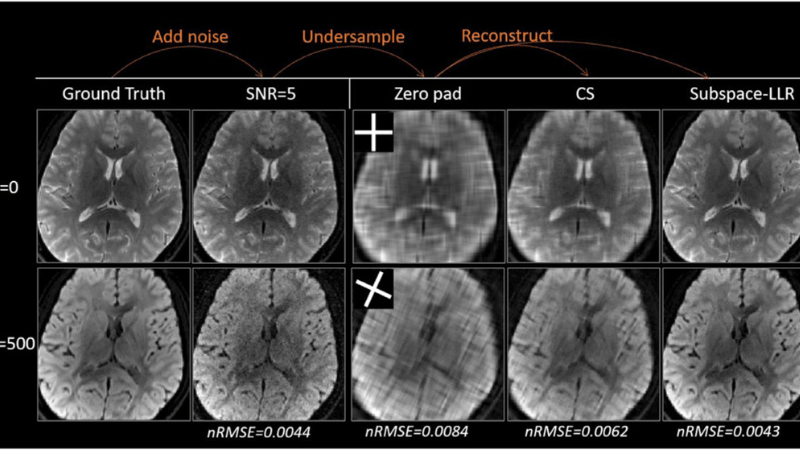

At IU School of Medicine, the Wu Lab continues to develop robust, fast, and super-resolution hybrid-diffusion imaging (HYDI) for studying the cortical gray matter and functionally distinct subfields of the deep-brain gray matter (e.g., the amygdala subfields and hippocampal subfields). Diffusion MRI on gray matter is not always straightforward. The major challenges are coarse imaging resolution, which causes signal contamination from cerebrospinal fluid and white matter; in cases of high spatial resolution, the image quality may suffer from a low signal-to-noise ratio. With respect to the cerebral cortical thickness of 1 to 4 mm, the current standard diffusion MRI studies with a modest resolution (isotropic voxel size of 2x2x2 = 8 mm3) suffer severe partial volume contamination from the surrounding tissues. We have developed an approach called RoSA (Rotating single-shot acquisition, Wen et al., Magnetic Resonance in Medicine 2018) to achieve a four-times-higher resolution (1x1x2 = 2 mm3) for diffusion MRI. We also use the CMRR multiband approach to achieve 1.25 mm isotropic resolution (1.25x1.25x1.25 = 2 mm3) for our routine HYDI scans. Building on the 1.25 mm acquisition resolution, we employed a Collaborative and Locally Adaptive Super-Resolution (CLASR) approach, which converts the redundancy information across multiple volumes of diffusion images to spatial resolution. The CLASR approach further brought the HYDI to a submillimeter super-resolution level (0.625 x 0.625 x 0.625 = 0.25 mm3) and enabled tractography within the hippocampal subfields (Elsaid et al., Neuroradiology 2022). The pursuit of high-resolution diffusion imaging was supported by multiple internal pilot funding and an external industrial contract.